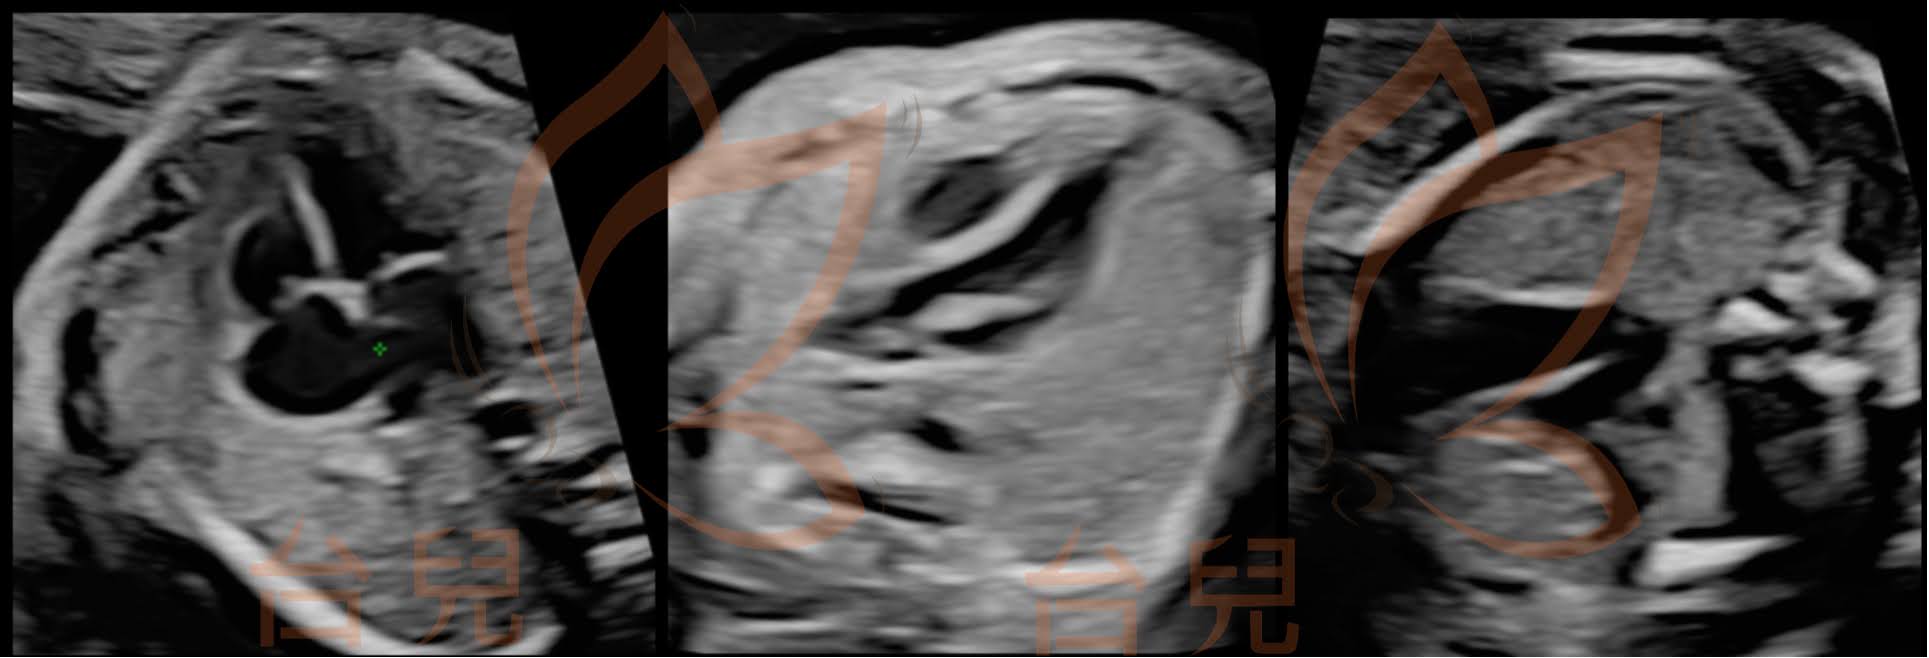

圖三(由左至右):三血管氣管切面至短軸切面。

紫色標記處為此個案的aorto-pulmonary window